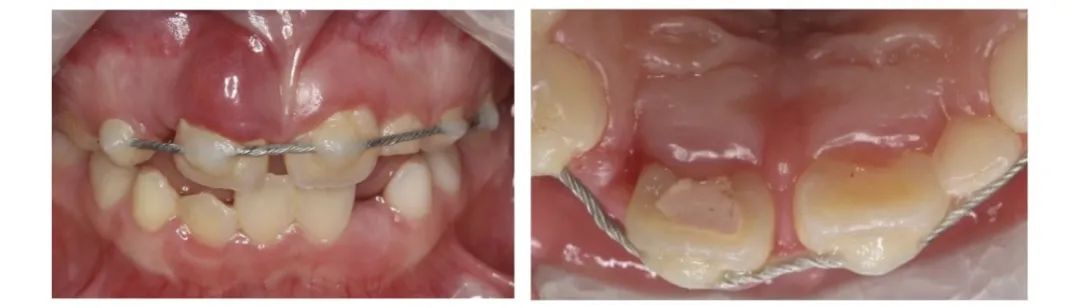

8岁的媛媛户外骑车玩耍时摔倒

导致右上大门牙完全脱出口腔

在当地医院行复位固定术后1周牙龈开始鼓包

媛媛的牙龈鼓了包又肿又痛